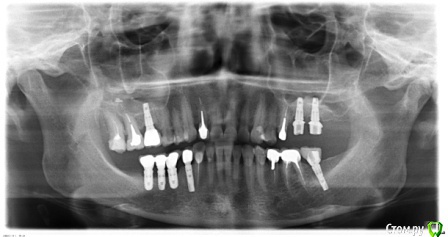

Cheremukha Опубликовано 15 апреля, 2016 Поделиться Опубликовано 15 апреля, 2016 Здравствуйте уважаемые доктора! Буду очень признательна за консультацию и обозначение тактики лечения. Субъективные жалобы: периодически возникающий глухой стук слева при жевании, хруст справа при открывании рта. Жжение языка. Боль в области уха справа. Головные боли в затылке (ежедневные) и сдавливание в области основания черепа. Боли и хруст появились после удаления зубов и имплантации (5 имплантов) 2 года назад. Потом последовало не совсем удачное протезирование, которое как раз привело к появлению щелчков и жжению языка. Я сменила ортопеда. Новый доктор убрал 10 коронок на коренных зубах и поставил временные коронки с завышением прикуса. На них у меня возникли сильные боли в челюстях, ухе, голове, я не могла их выдержать и попросила их снять, что доктор и сделал. Уже месяц я хожу без коронок. Сейчас у меня отсутствуют: слева вверху и внизу концевые зубы начиная с 5-го и справа внизу концевые зубы начиная с 4-го. Стоят абатменты и вкладки, а коронок на них нет. МРТ (3-х месячной давности): Частичная вентральная дислокация диска правого ВНЧ сустава с полной репозицией. Артроз левого ВНЧ сустава 0-1ст. Малая частичная вентральная дислокация диска с полной репозицией при открывании рта и формированием частичной медиальной дислокации диска. МР-признаки функциональной перегрузки правой латеральной крыловидной мышцы. Делала боковую ТРГ, заключение не дали, снимок прилагаю. Так же прилагаю орто-снимок. Ортопед, у которого я была на консультации предлагает поставить временные коронки, которые он будет подтачивать под мое удобное положение челюсти, а потом запротезируют постоянными коронками. Скажите пожалуйста, достаточно ли в моем случае протезирования без ношения капы? Какая тактика лечения наиболее приемлема в моем случае? З.Ы. Еще сложность в том, что у меня стоят импланты Астра и Лико. Оказалось, что очень непросто найти в Москве ортопеда, работающего на обоих системах. Ссылка на комментарий